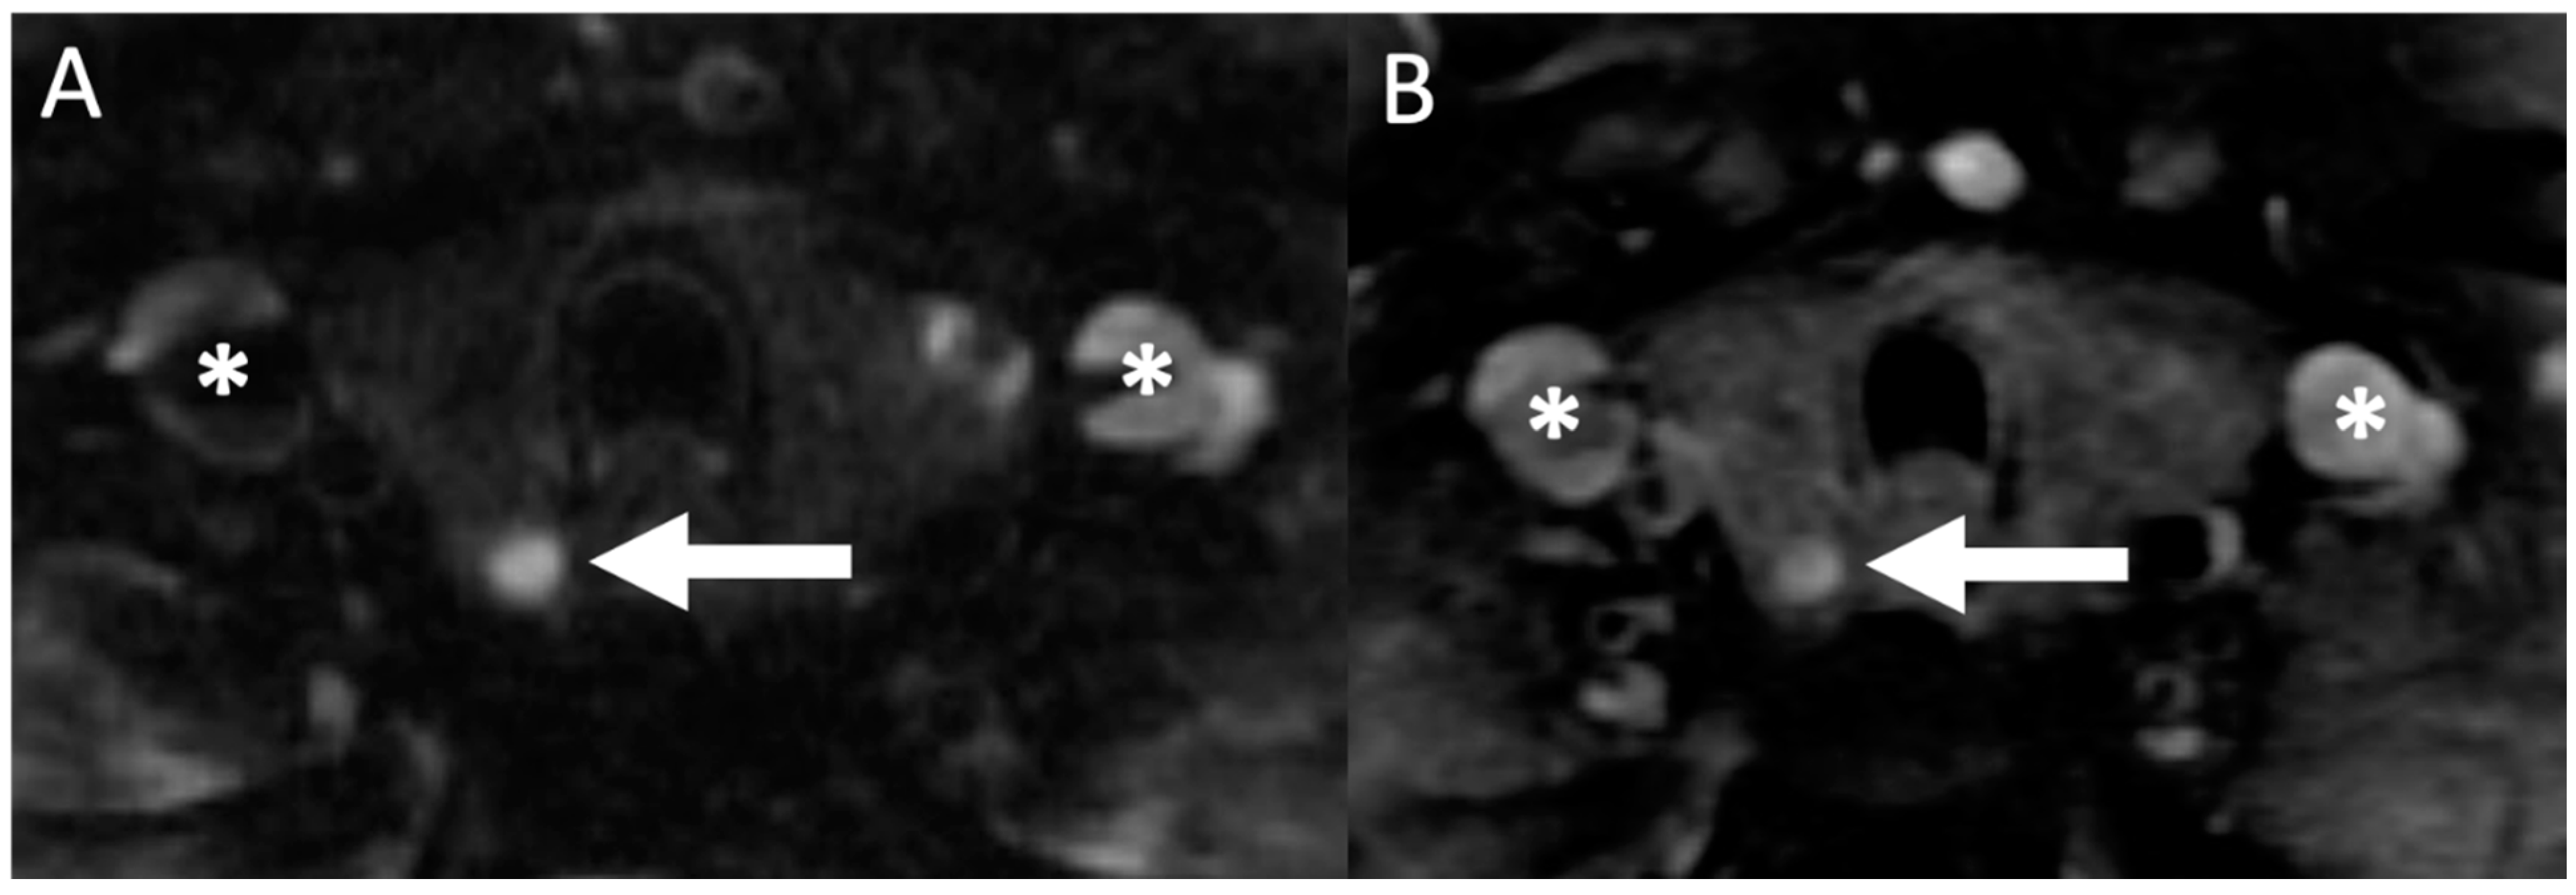

On MRI, benign parathyroid lesions typically demonstrate a well-defined border and an elongated morphology, usually best evaluated on T2 weighted imaging (Figure 7) [100]. In addition, a cleavage plane is commonly seen separating the parathyroid gland from the thyroid gland on the T2 out-of-phase sequence [100]. Parathyroid lesions can show variable signal characteristics on T1 and T2 weighted imaging but are usually bright (hyperintense) and homogenous appearing on T2 (96%). A marbled appearance can also sometimes be seen [100]. Following intravenous gadolinium contrast administration, rapid enhancement in the arterial phase is observed [101,102], which has been shown to increase diagnostic confidence [100,103]. Rarely, hemorrhage, fat (such as in a lipoadenoma) or fibrosis may result in atypical imaging features on MRI [98,100].

Figure 7.

Magnetic resonance imaging (MRI): 71-year-old woman with hypercalcemia. Axial T2 weighted imaging (A) showing a hyperintense (bright) nodule posterior to the right thyroid lobe (white arrow) with subsequent axial (B) gadolinium contrast enhanced T1 weighted imaging showing an enhancing lesion (white arrow), subsequently resected confirming the presence of parathyroid adenoma on histopathology. Asterisks (*) denote the location of the bilateral jugular veins.